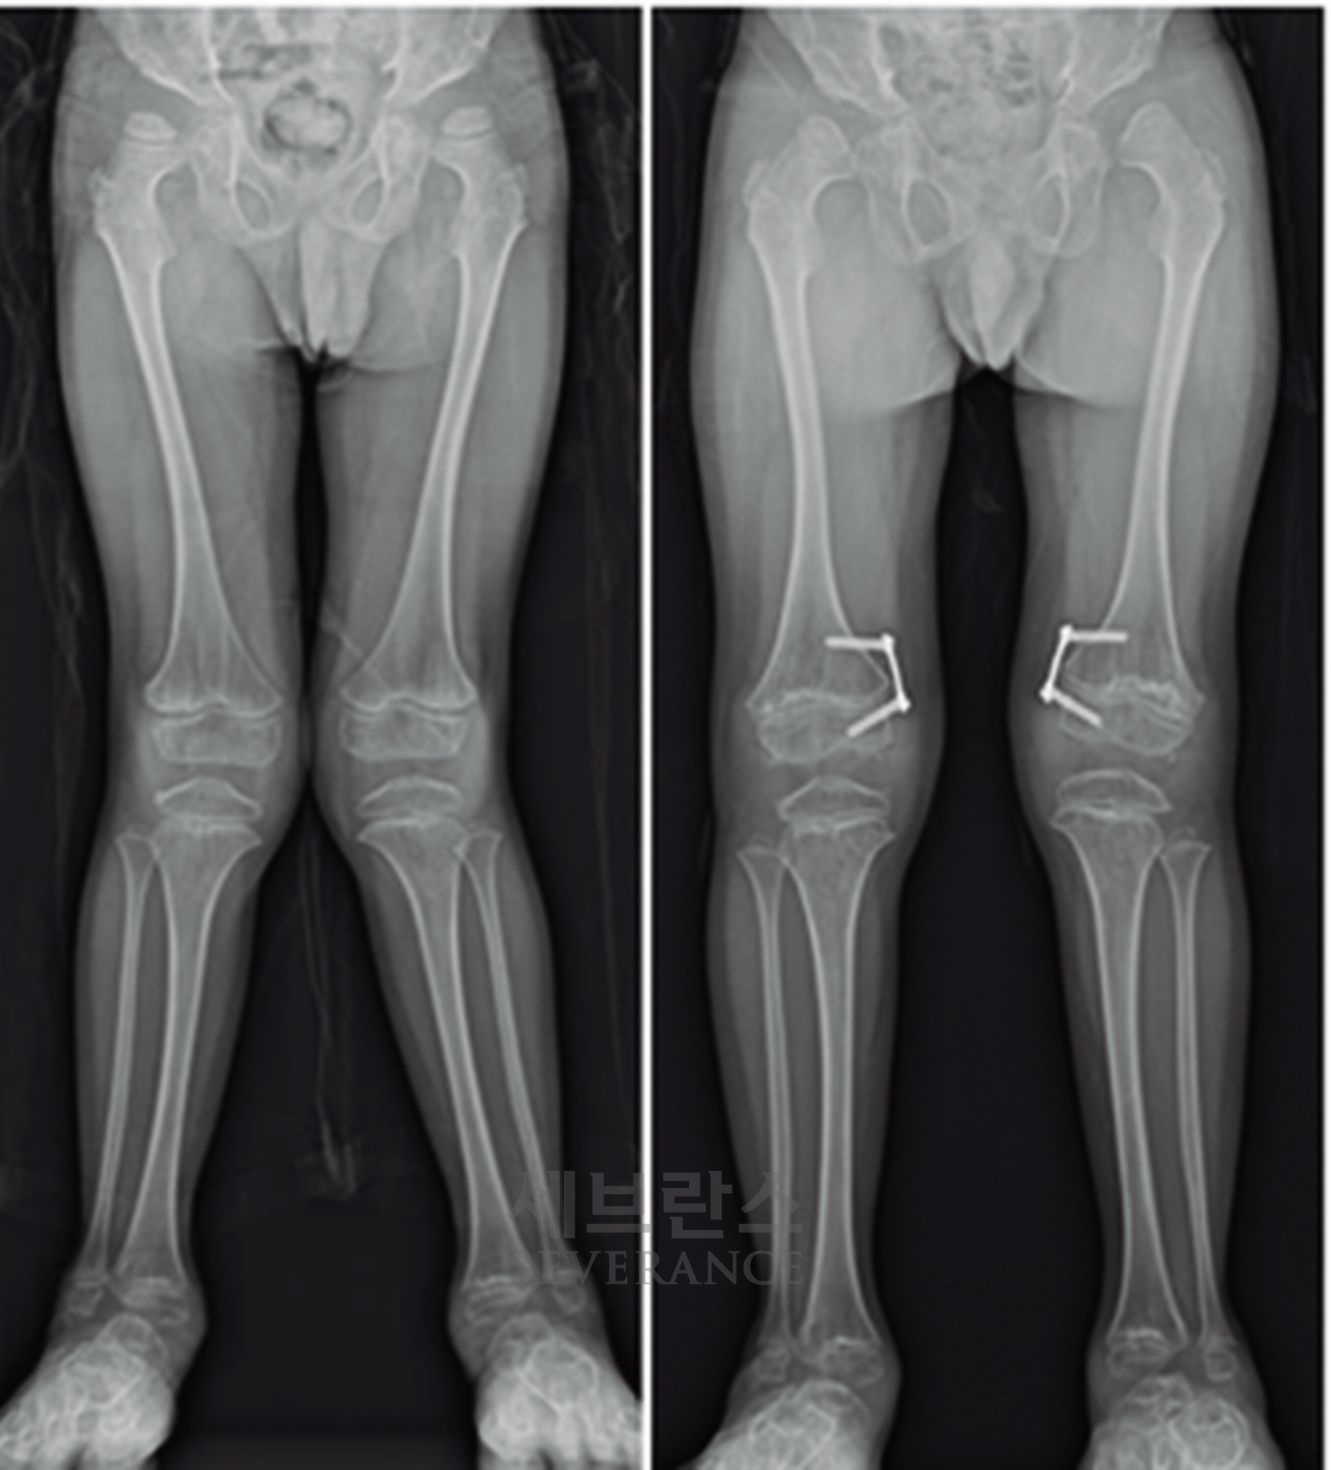

• 골연장술

양쪽 팔다리의 길이 차이가 큰 경우에 주로 시행하는 수술로, 외부 고정 장치나 내부 금속정을 이용해 뼈를 서서히 늘려 균형을 맞추는 방법입니다. 대체로 외부 고정 장치를 많이 사용하는데, 연장 기간 동안 날마다 정해진 횟수만큼 뼈를 조금씩 늘려야 하고, 핀 주변 소독도 꾸준히 해줘야 합니다. 연장된 뼈가 단단히 붙는 데도 수개월이 걸리기 때문에 환자와 보호자의 인내가 필요합니다.

성장판 손상으로 발생한 좌측 외반슬하지부동에 대해 골연장술과 교정술을 동시에 시행해 치료한 환아